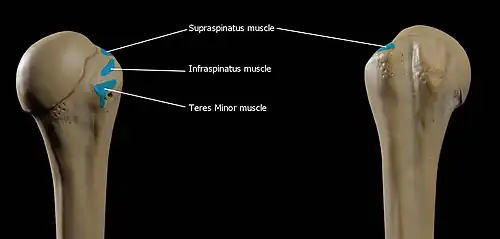

Greater tubercle

The greater tubercle (tuberculum majus; greater tuberosity) is a large, posteriorly placed projection that is placed laterally. The greater tubercle is where supraspinatus, infraspinatus and teres minor muscles are attached. The crest of the greater tubercle forms the lateral lip of the bicipital groove and is the site for insertion of pectoralis major.

The greater tubercle is just lateral to the anatomical neck. Its upper surface is rounded and marked by three flat impressions: the highest of these gives insertion to the supraspinatus muscle; the middle to the infraspinatus muscle; the lowest one, and the body of the bone for about 2.5 cm. below it, to the teres minor muscle. The lateral surface of the greater tubercle is convex, rough, and continuous with the lateral surface of the body.[2]

The deltoid originates on the lateral third of the clavicle, acromion and the crest of the spine of the scapula. It is inserted on the deltoid tuberosity of the humerus and has several actions including abduction, extension, and circumduction of the shoulder. The supraspinatus also originates on the spine of the scapula. It inserts on the greater tubercle of the humerus, and assists in abduction of the shoulder.

The infraspinatus and teres minor insert on the greater tubercle, and work to laterally, or externally, rotate the humerus. In contrast, the subscapularis muscle inserts onto the lesser tubercle and works to medially, or internally, rotate the humerus.

The four muscles of supraspinatus, infraspinatus, teres minor and subscapularis form a musculo-ligamentous girdle called the rotator cuff. This cuff stabilizes the very mobile but inherently unstable glenohumeral joint. The other muscles are used as counterbalances for the actions of lifting/pulling and pressing/pushing.